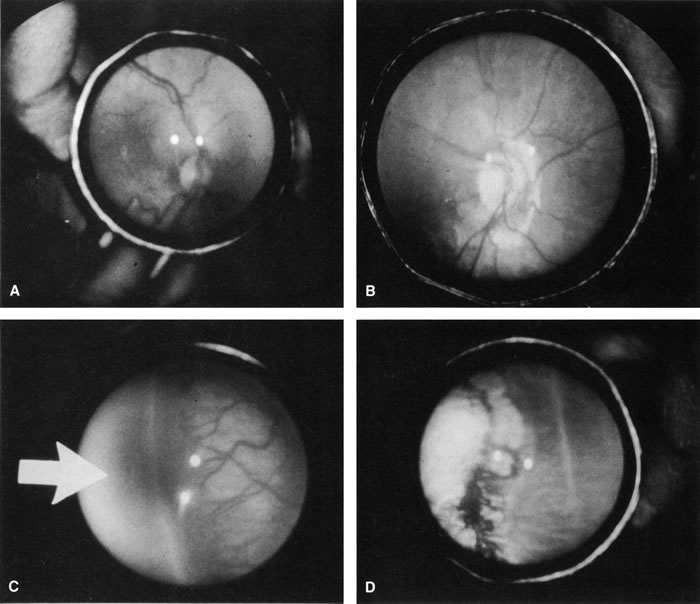

The desired outcome after cryotherapy is regression of both plus disease and extraretinal fibrovascular proliferation (Fig. 4). Without regression, features of unfavorable outcome, both anatomic and functional, may develop. The structural and functional benefits of cryotherapy in eyes with threshold disease have been demonstrated by the CryoROP study at 1 year, 3 ½, and 5 ½ years post enrollment.11,19 At 10 years post enrollment structural outcome was unfavorable in 47.9% of control eyes versus 27.2% of treated eyes. Unfavorable functional outcome (Snellen visual acuity of 20/200 or worse) was identified in 62.1% of control eyes versus 44.4% of treated eyes at 10 years. The percentage of eyes with 20/40 or better visual acuity was similar for both treated (25.2%) and untreated (23.7%) eyes at 10 years with no statistical difference between the two groups.10

Fig. 4. Preoperative (A) and postoperative (B) appearance of the posterior pole of an infant treated for threshold ROP with cryotherapy. Note the regression of plus disease after treatment. Preoperative (C) and postoperative (D) appearance of the retinal periphery of the same infant. Avascular zone (arrow). Note the regression of the extraretinal fibrovascular proliferation and the cryotherapy scarring.

A reduction in both plus disease and extraretinal fibrovascular proliferation should be seen by 1 week after treatment.